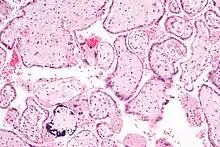

Micrograph of a cytomegalovirus (CMV) infection of the placenta (CMV placentitis). The characteristic large nucleus of a CMV-infected cell is seen off-centre at the bottom-right of the image. H&E stain.